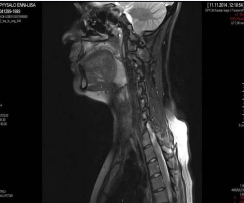

Patient’s clinical course was unusual since after initial presentation and patient several times repeatedly developed the same symptoms. Patient was admitted within 6 months in total 4 times in the ward because of dysphagia, sore throat and subjective shortness of breath. There was no stridor at any point. Fever was present at the time of first and third admission. Since swelling of epiglottis and lingual tonsil were present, patient received high doses of corticosteroids intravenously and per os. There was no swelling of the vocal cords at any point and airway was patent. Each admission lasts between 4 to 7 days. CRP was elevated every time that patient was admitted. Leukocytosis was present during the first, third and fourth admission of the patient. Since patient had fever and inflammation parameters were elevated, patient received in total two courses of intravenous antibiotics and five courses of antibiotics per os. Along with a follow-up appointment between the second and third admission, a neck MRI was taken and it revealed a hypertrophy of lingual tonsil and neck lymphadenopathy. During the third admission of the patient in the hospital, patient complained also for tenderness to her ankles. A thorax x-ray showed no pulmonary infiltrates but visualization of the bronchus close to the hilum of the lung was prominent. During the admission, patient’s dysphagia and airway symptoms were more prominent. Thus, different laboratory tests were carried out to exclude diseases such as sarcoidosis and vasculitis. A computed tomography (CT) body scan was ordered. CT imaging showed one solitary condensed triangularshaped 6-mm shadow in right lung (in the middle lobe). In the left ovary, there was a 2.8 cm x 4 cm cyst. In SI-joints, there was some mild sclerosis. No pathological lymphadenopathy was found. Three days later, a biopsy was taken from the lingual tonsil. Histopathological examination of lingual tonsil, revealed the presence of necrotizing granulomatous inflammation (non caseating granulomas with giant cells). There was no evidence of sarcoidosis and tuberculosis was excluded figure 1.

Magnetic resonance imaging revealed hyperthophy of the lingual tonsil neck lymphadenopathy.

Figure 1: Magnetic resonance imaging revealed hyperthophy of the lingual tonsil neck lymphadenopathy.